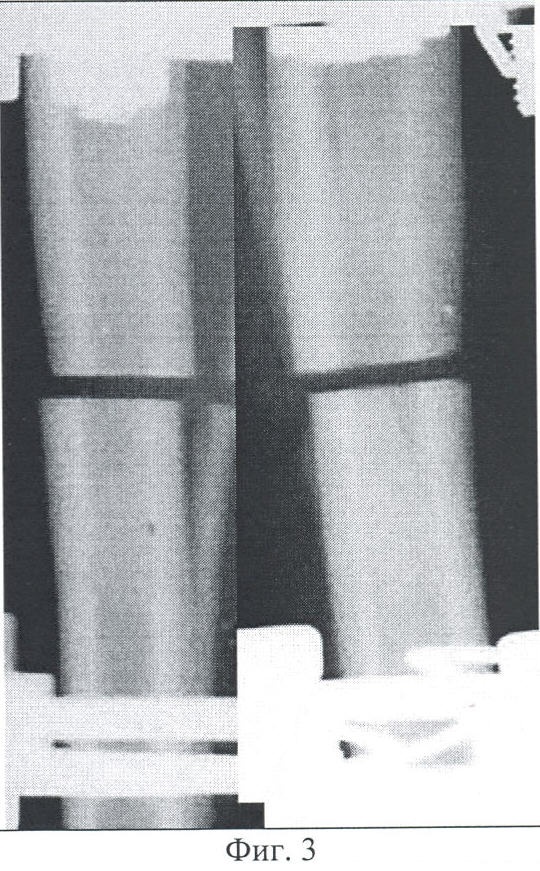

Фиг.5 – копия рентгенограммы костей голени согласно изобретению, 30 суток фиксации после компрессии, 42 дня опыта.

К 30 суткам после компрессии на рентгенограммах линию перелома перекрывают плотные гомогенные тени. Эндостальная реакция в отломках затухает. Периостальные напластования заметно компактизируются (Фиг.5). При клиническом исследовании патологическая подвижность и болезненность в области остеотомии не определяются, что является основанием для прекращения фиксации аппаратом.